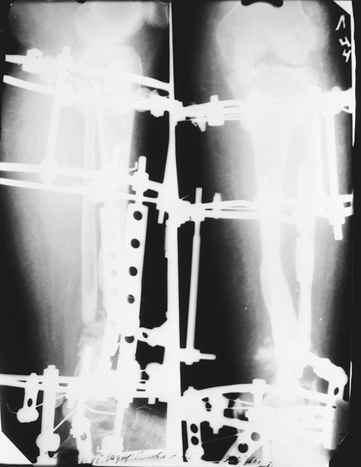

Случай, который я представляю, был сделан мной около 20 лет назад в Кургане.

Женщина 28 лет, пошедшая 13 предыдущих оперативных вмешательств по-поводу ВПБ имела 9 см. укорочения.

На первом этапе аппаратом Илизарова закрыто устранена деформация голени.

На втором этапе произведёно освежение краёв костных фрагментов б/б и м/б костей с приданием проксимальному фрагменту б/б кости впалой, а дистальному выпуклой формы, открытие канала проксимального фрагмента и погружной остеосинтез, а также остеотомия б/б кости в в/3 и м/б кости на границе с/3 и н/3 голени. Больной проводился одновременный бифокальный компрессионно-дистракционный остеосинтез. Достигнуто 11 см. удлинение и сращение ВПГ.

Срок лечения 11 месяцев. Наблюдение 2 года.